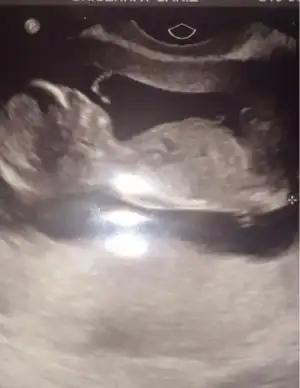

kızlar birde bize bakarmısınız ben anlayamadım şu nub teorisini![]()

simdi nedir bu genital nub

yok 30°lik bir aciyla yukari dogru bakiyorsa %99 oglunuz olacak demektir simdi bi kac ornek resimler daha koyacagim kiziminkide dahil

Eki Görüntüle 473829 bu bir erkek bebek genital nub cikintisi gayet yukarda

Eki Görüntüle 473831 simdi burada cikintilara bakin eger bel popo cizgisine paralel ise kiz

yok 30 derecelik bir aciyla yukari bakiyorsa erkek

yabancilarin hepsi biliyor bunu biz neden eksik kalalim gayet bilimsel simdi ellerinde11 12 13 ultrason fotografi olanlar alsin hemen baksin yada koyalim buraya yorumlayalim

Eki Görüntüle 473837 bu benim kizim cikinti gayet net ve ortada ve ben kizim diyooo